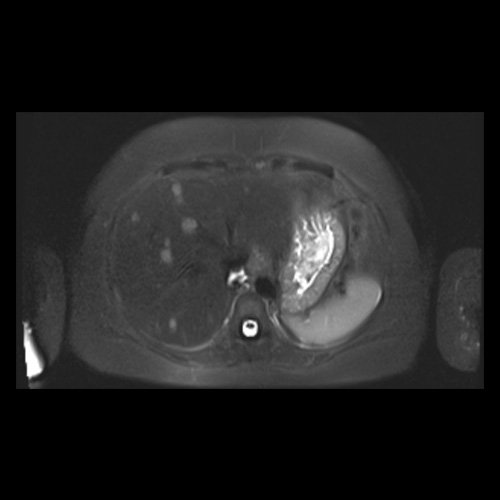

RMN de abdomen con contraste endovenoso (14/02/26)  Corte coronal (T2): adenoma suprarrenal izquierdo; lesión hepática redondeada hiperintensa redondeada en segmento VII.

• RMI abdomen y pelvis con contraste EV (14/02/26): En las bases pulmonares se visualizan atelectasias laminares bibalsales. No se identifica derrame pleural. El hígado es de forma, tamaño y situación normal. La superficie es lisa, los bordes son agudos. Se observan múltiples lesiones sólidas de distribución difusa, levemente hiperintensas en T2, con restricción en difusión y realce homogéneo tras la administración de contraste EV, la de mayor tamaño de 15 mm en segmento VII. Sugiero conocimiento histológico. La vía biliar intra y extrahepática es de calibre conservado. La vesícula biliar es de forma y situación habitual, sus paredes son finas y no presenta imágenes hipointensas en su interior, que sugieran la presencia de litiasis. El bazo es de forma, tamaño y situación normal, sin efectos de masa focales. El páncreas es de forma, tamaño y situación normal, sin efectos de masa. El Wirsung es de calibre conservado. Glándulas adrenales de forma, tamaño y situación normal, sin efectos de masa. Ambos riñones son de forma, tamaño y situación normal, con adecuada diferenciación córtico subcortical. No se observan alteraciones a nivel de la vía excretora. No se observan adenomegalias retroperitoneales ni intraperitoneales. La aorta abdominal, las arterias iliacas primițivas, internas, externas y femorales son de trayecto y calibre normal La vena cava inferior, las venas ilíacas primitivas, internas, externas y femorales son de trayecto y calibre normal. No impresionan alteraciones a nivel del tracto gastrointestinal. La vejiga es de paredes finas, normalmente distensibles, sin evidencia de lesiones endoluminales ni parietales. Mioma transmural en hoja anterior de útero que mide 55 x 47 mm sin signos de complicaciones. Imagen ovalada de contenido líquido que mide 65 x 52 mm en el espesor del tejido celular subcutáneo de región antero-superior de muslo derecho, por delante de músculo sartorio, que no presenta realce tras la administración de contraste EV.